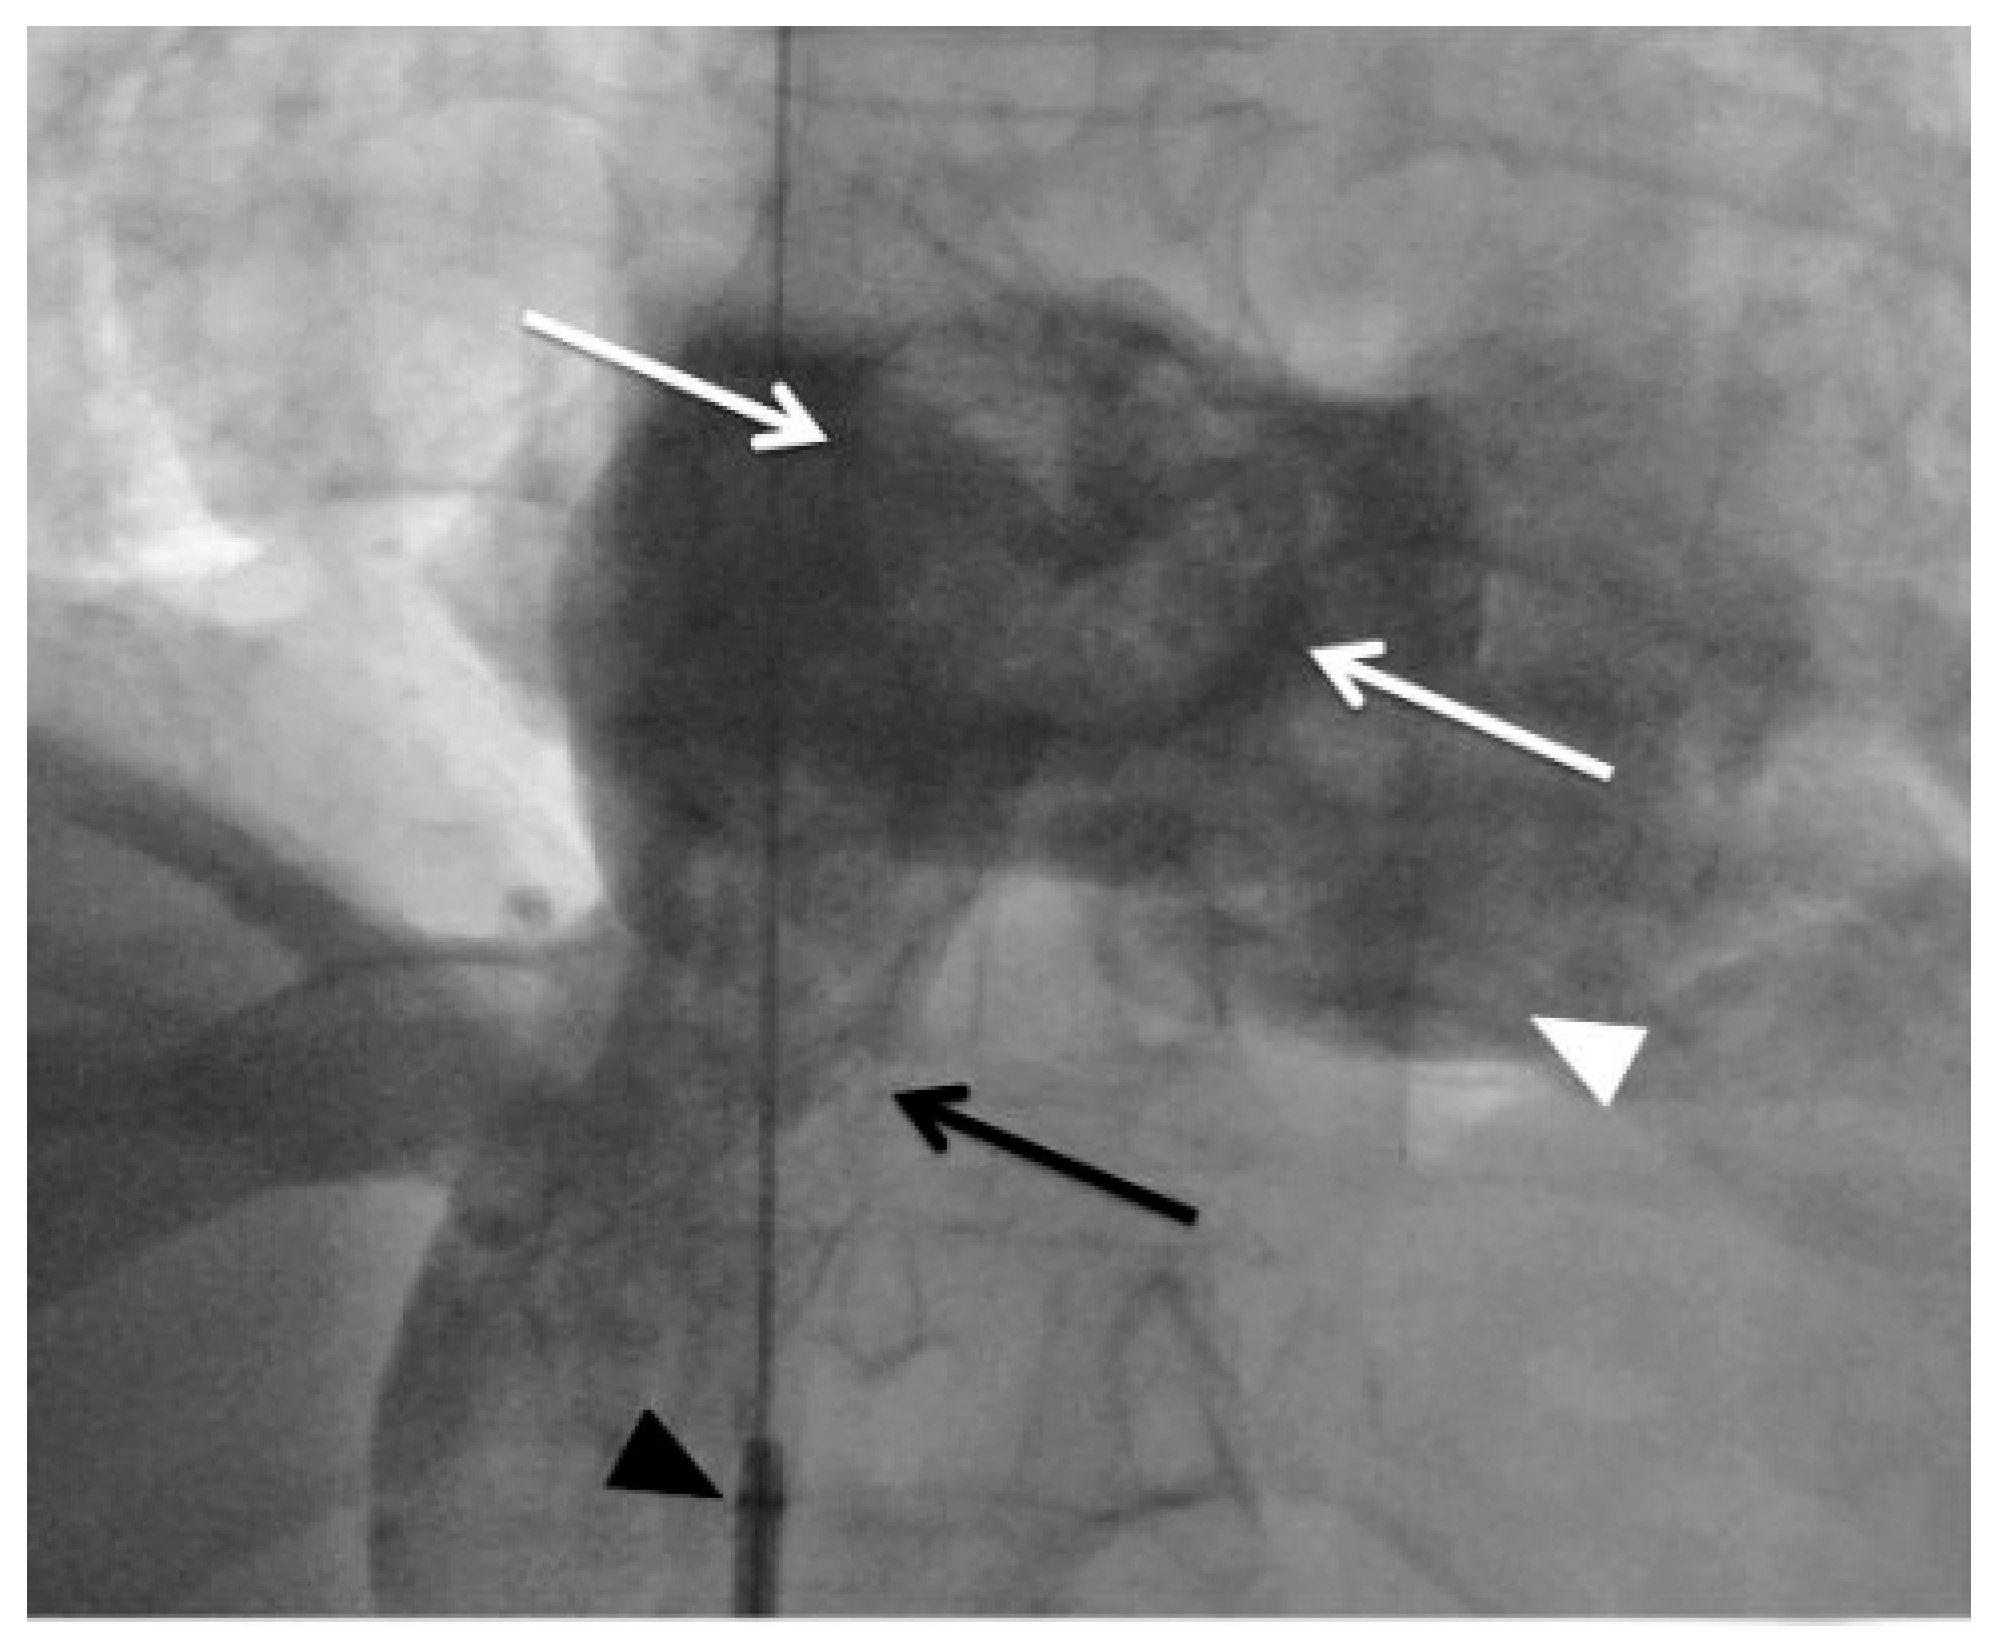

Figure 1. Inferior vena cavography in anterior-posterior (AP) projection through an 8 F Multipurpose guiding catheter (black arrowhead) positioned in the inferior vena cava demonstrating a large right atrial thrombus (white arrows) at the level of the fossa ovalis. White arrowhead = right ventricle; black arrow = inferior vena cava.